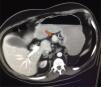

He was admitted to the GI service from 07-10-2011 to 20-11-2011 due to a nonspecific abdominal pain. During the admission, he presented repeated vomiting, subsequent tests show the presence of chronic pancreatitis, initiating enzymatic treatment with slight clinical improvement. Continues with digestive pain, marked anxiety, much emotional liability that made the communication and physical examination difficult. It should be noted that the gastrointestinal symptoms were so unspecific that sometimes improved with psychological support from nursing, NSAIDs, antiemetics or anxiolytics. The persistence of nonspecific abdominal pain, especially during hemodialysis sessions, suggests an underlying disease not yet diagnosed. An abdominal ultrasound was performed, with no relevant findings, except for previously known kidney disease. Abdominal CT was requested, showing a dubious mass of 2cm protruding in the upper edge of the body of the pancreas near the isthmus, as well as a Bochdalek hernia.

The patient was referred to the surgery and endocrinology service and was diagnosed with a probable neuroendocrine tumor. As a treatment, a subcostal exploratory laparotomy was performed, observing a highly vascularized mass 2.5cm in diameter without apparent contact with the Wirsung canal (Fig. 2). Stability of the lesion and Ki-67 less than 2% is appreciated, so it is decided to enucleate the tumor that was performed without any incidents. The anatomopathological diagnosis showed a mass in the body of the pancreas of 2cm in diameter, G1 of the 2010 WHO classification, which respects the surgical border, although it is located at less than 1mm from surgical border. Chromogranin to isintaphysin: (+) Ki-67: low rate of cell proliferation (−1%). Lymph node in greater curvature, adipose tissue without histological alterations. Peritoneal solitary cyst. The patient remained stable in the postoperative period, being transferred to the internal medicine for recovery.